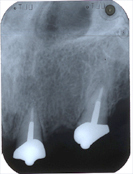

In den Abb. 2 und 3 sind auf zwei Kontrollröntgenbildern neun Jahre nach der Wurzelbehandlung (Endodontie) einwandfreie, entzündungsfreie Knochenverhältnisse im Oberkiefer sichtbar.